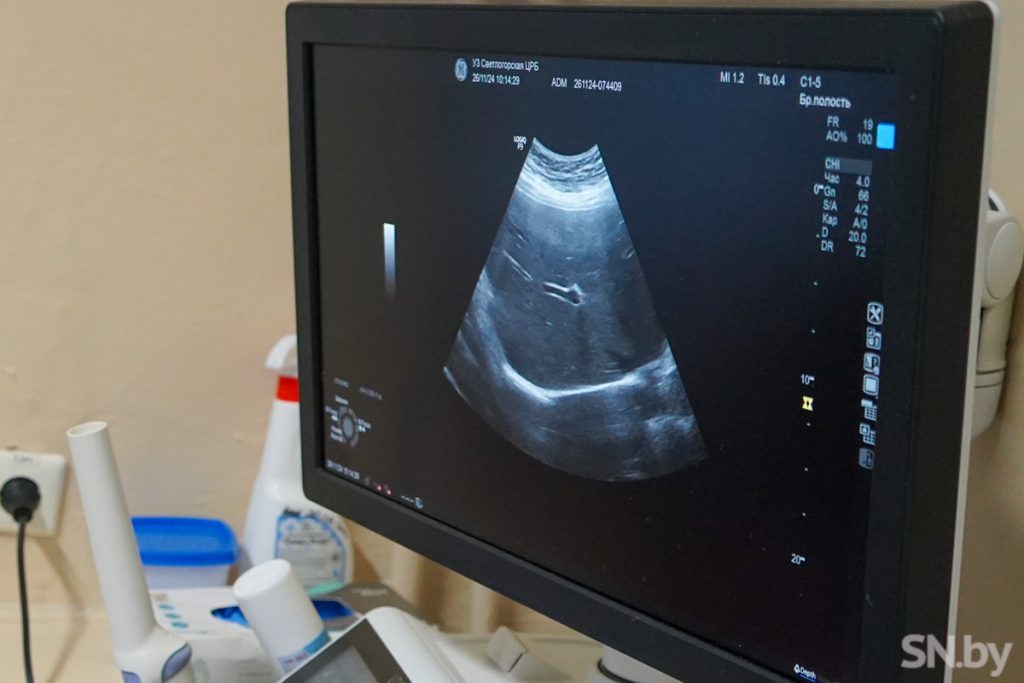

Работает она на аппарате экспертного класса, который получили в 2022 году: «Мы его ждали, у него прекрасная визуализация, 4 датчика, это высокоточное оборудование дает большие возможности для процедуры УЗИ», — поясняет специалист.

Врач ультразвуковой диагностики — профессионал широкого профиля, ему приходится знать патологии почти всех органов и систем организма. Профессия требует серьезных знаний и все время ставит интересные задачи. И, конечно, проведение УЗИ для беременных — любимая специализация Анны Якубенко. «УЗИ беременным нужно делать четко в определенные сроки, чтобы заметить проблемы и своевременно принять меры по их решению, — объясняет Анна Сергеевна. – Особенно приятно показывать будущим мамам малышей и вручать первые их фотографии. Кто-то просит озвучить пол ребенка сразу, кто-то приберегает информацию для гендер-пати. В этом случае я стараюсь выполнить просьбу, но только если уверена на 100%. Бывает и по-другому: одна пациентка просила не озвучивать пол ребенка до самых родов…»

— УЗИ – простой, безопасный и сравнительно недорогой метод обследования. С его помощью удобно обследовать все мягкие ткани человека – от глазного яблока до мышц. Ему не мешают кардиостимуляторы или искусственные суставы, как в случае с КТ и МРТ. Часто врачи назначают УЗИ как первое, предварительное обследование. Если выявляются какие-то патологии, то в дальнейшем их изучают уже с помощью более точных методов, — говорит Анна Сергеевна.